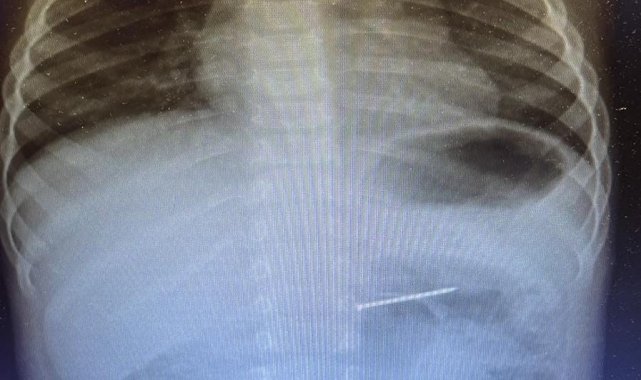

Burdur'un Bucak ilçesinde yaşayan 2 yaşındaki bir çocuk, yuttuğu çivi nedeniyle ailesi tarafından acil sağlık ekiplerine bildirildi. 112 Acil Servis aracılığıyla Süleyman Demirel Üniversitesi (SDÜ) Hastanesi'ne sevk edilen çocuk, Çocuk Gastroenteroloji ve Endoskopi Birimi'nde değerlendirmeye alındı. Radyolojik inceleme sonucu yaklaşık 4 santimetre uzunluğundaki çivinin midedeki konumu tespit edildi ve hemen endoskopik müdahale yapıldı. Yapılan işlemle çivi, herhangi bir komplikasyona yol açmadan başarılı şekilde çıkarıldı. Hasta, kısa süreli gözlem amacıyla serviste takip altına alındı ve sağlık durumu stabil şekilde taburcu edildi.

Çocuk Sağlığı ve Hastalıkları Anabilim Dalı'ndan Uzman Dr. Abdülkerim Elmas, özellikle 6 ay ile 3 yaş arasındaki çocuklarda yabancı cisim yutma olaylarının sık görüldüğünü ve hayati tehlike oluşturabileceğini belirtti. Dr. Elmas, "Pil, mıknatıs ve çivi gibi nesneler sindirim sistemine zarar verebilir. Aileler ev ortamında bu tür tehlikeli objeleri çocukların erişemeyeceği yerlerde tutmalı. Ani ağlama, yutma güçlüğü, kusma veya karın ağrısı gibi durumlarda acilen bir sağlık kuruluşuna başvurulmalıdır" dedi.